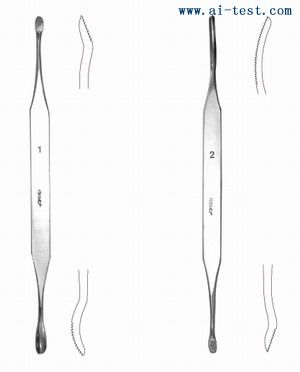

AM5101861 č└ė├õS č└ų▄ 1# ų▒ ░╦ĮŪ▒·

AM5101862 č└ė├õS č└ų▄ 2# ėęÅØ ░╦ĮŪ▒·

AM5101863 č└ė├õS č└╣Ū 1# ╝ŌłA/╝ŌłA ▒Ō▒·

AM5101864 č└ė├õS č└╣Ū 2# ķLłA/╝ŌłA ▒Ō▒·

AM5101865 č└╣ŪÕN 18cm ╦▄▒·

AM5101866 č└╣ŪÕN 15cm Įī┘▒·